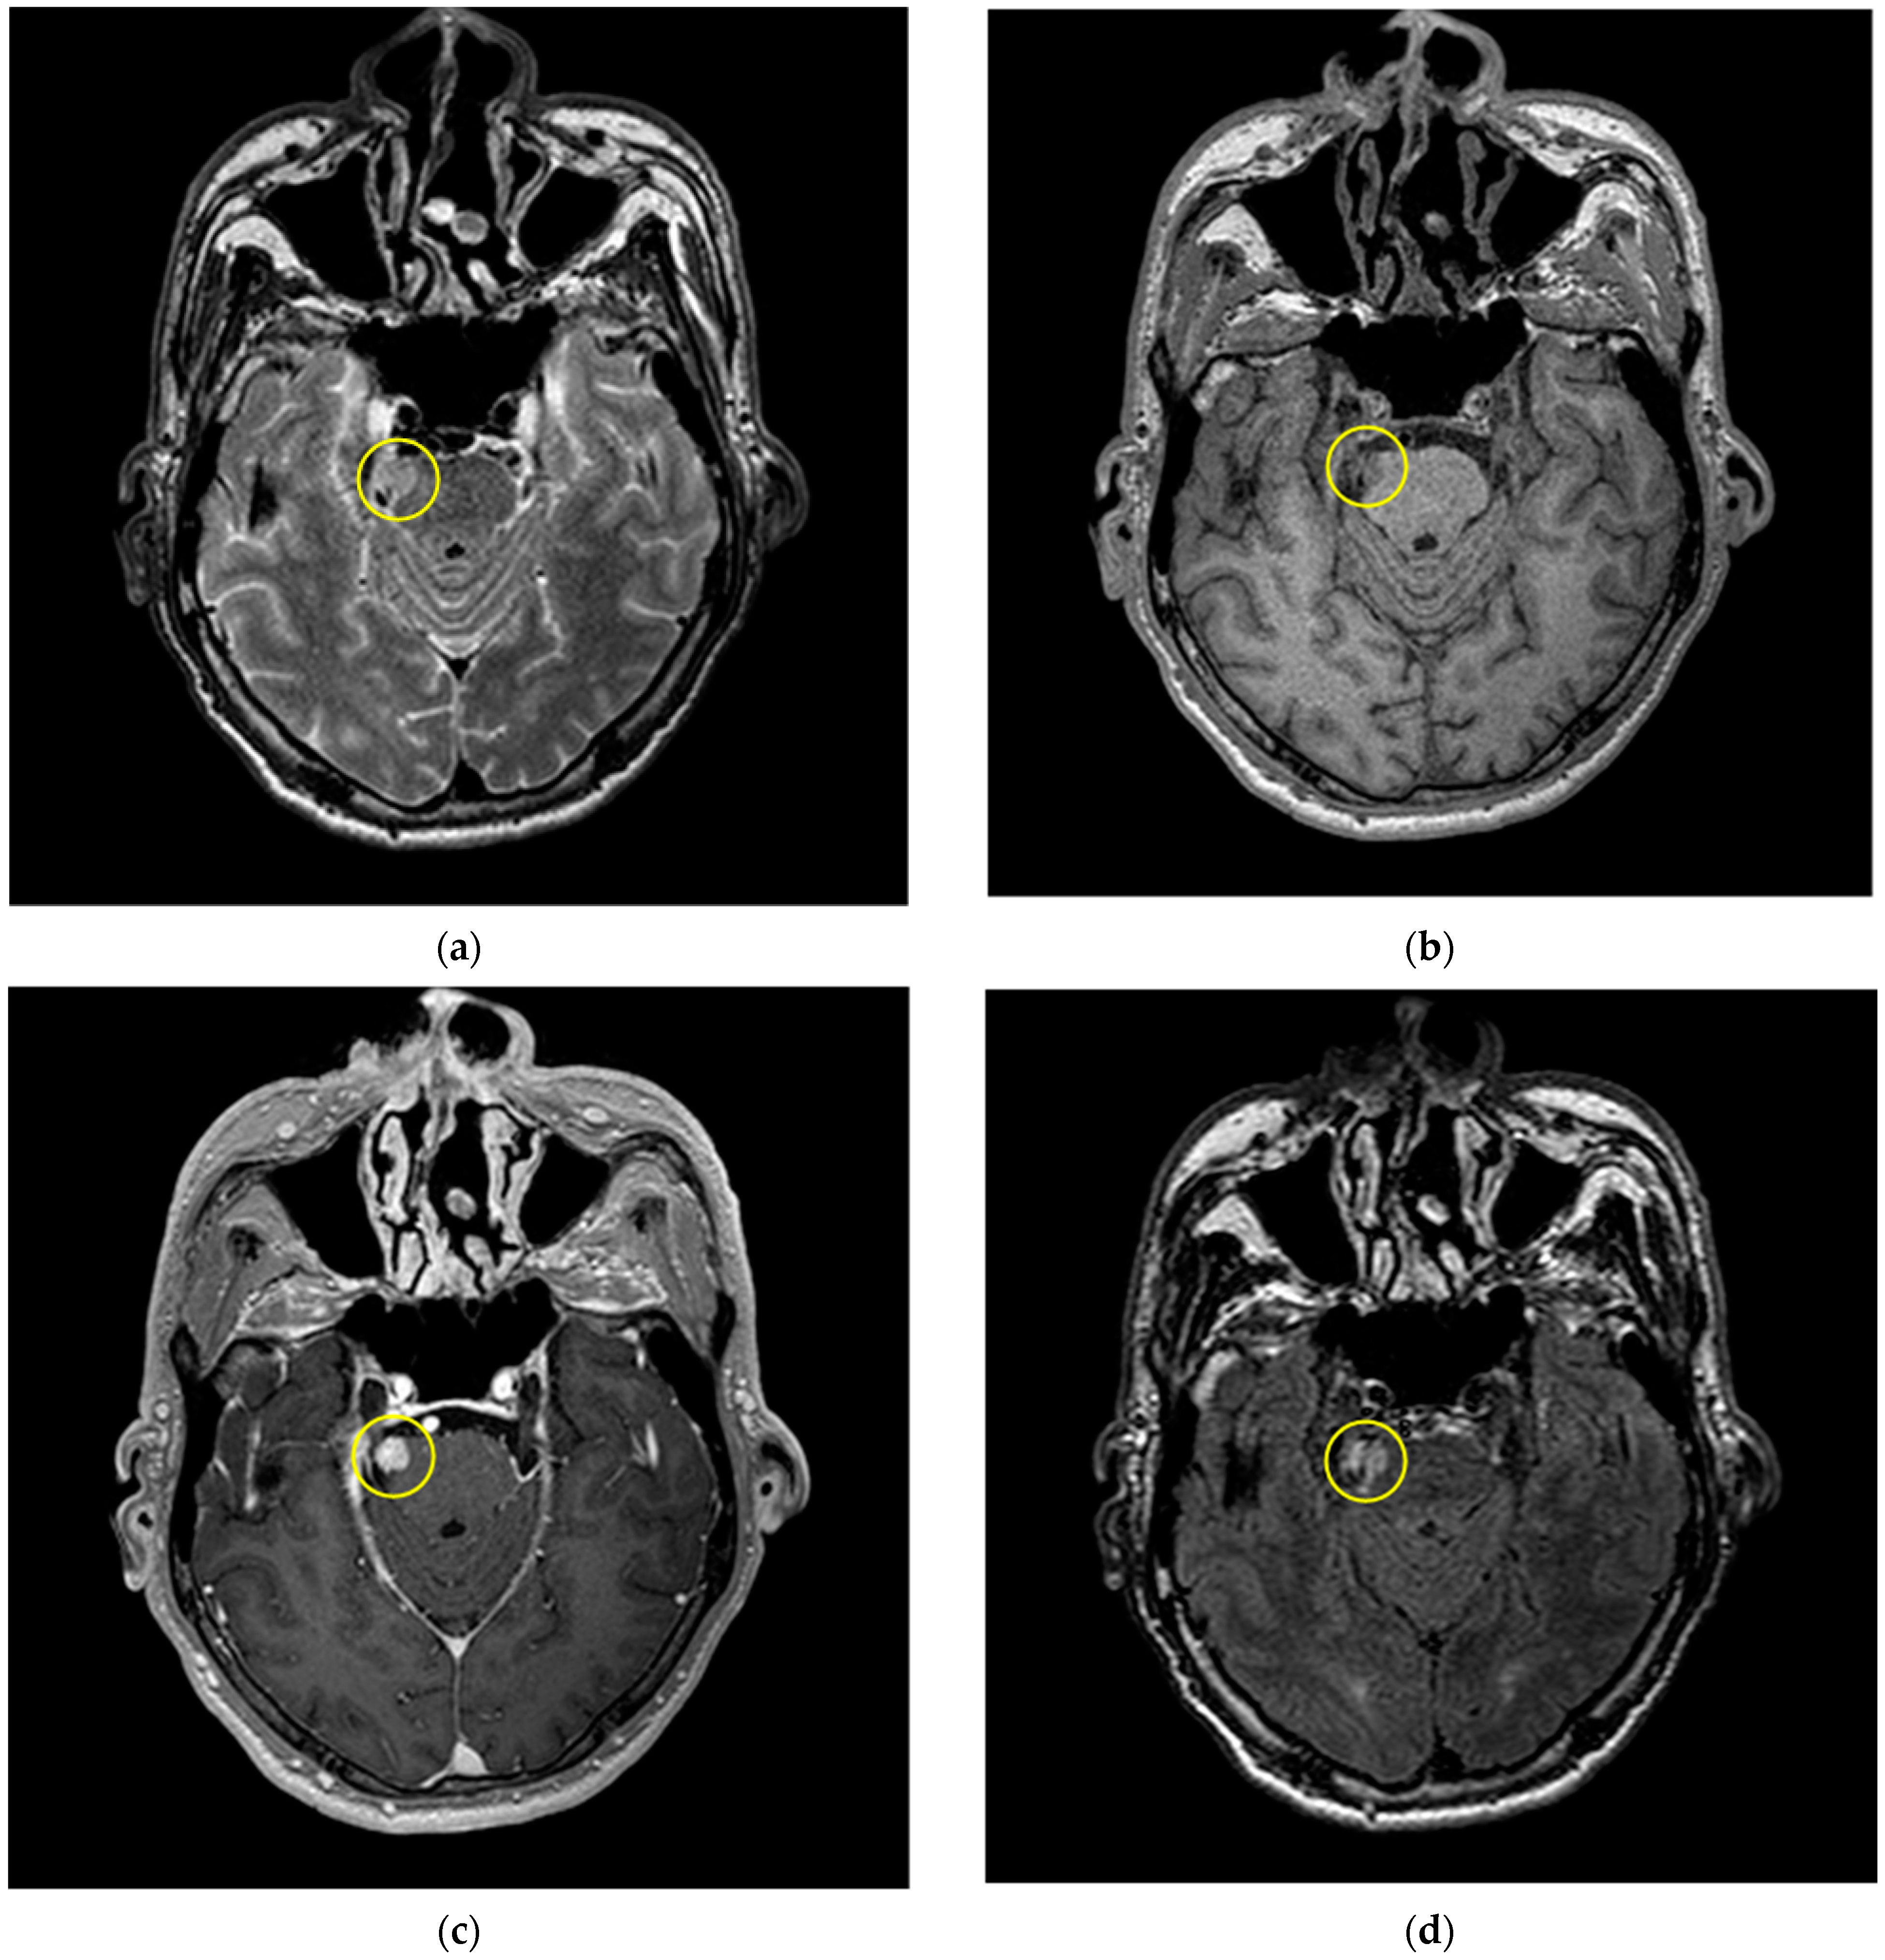

2.1. MRI Dataset

3.1. Image Pre-Processing